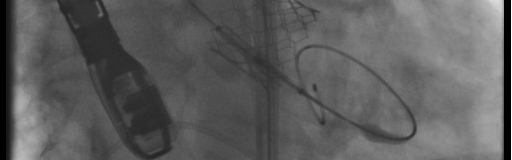

The Interventional Cardiology Fellowship Program is a one-year, ACGME-accredited training program designed to prepare the fellow for the practice of high quality interventional cardiovascular medicine. This high volume interventional program will provide the fellow with robust didactic and hands-on training in preparation for the ABIM interventional cardiology boards and a successful career. Qualified candidates who have completed three years of cardiology fellowship will be considered for the program.